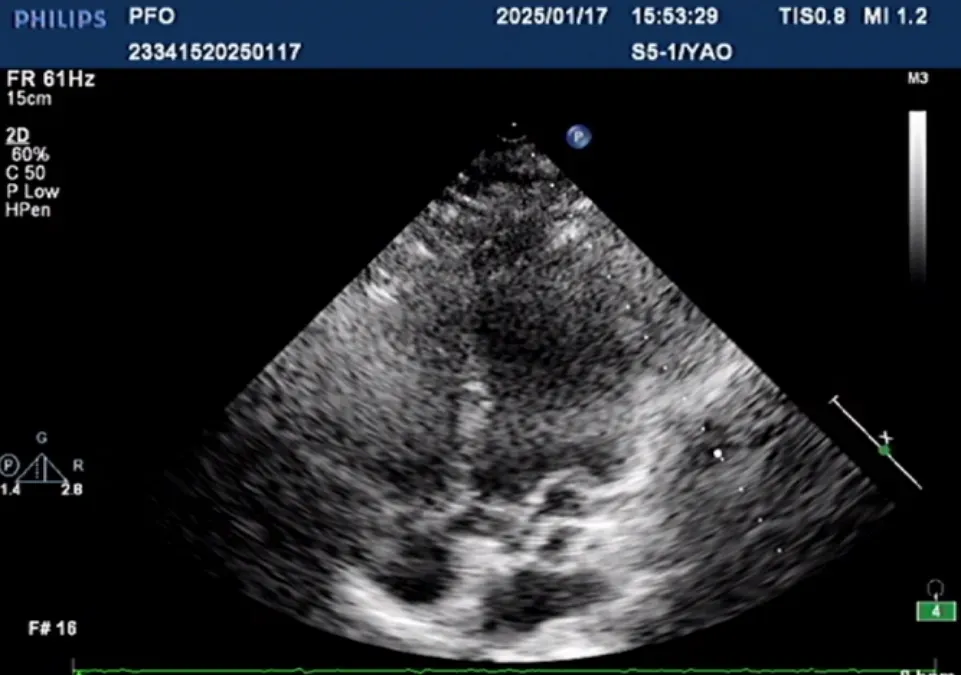

導(dǎo)絲通過卵圓孔進(jìn)入左房